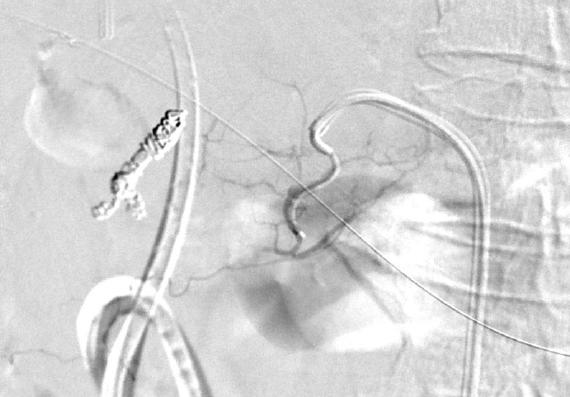

经肠系膜上动脉-结肠中动脉-肠系膜下动脉选择性动脉造影显示内漏还来自于该动脉 |

经微导管栓塞

(NBCA : Lipiodol = 1 :4)

NBCA 栓塞后 |